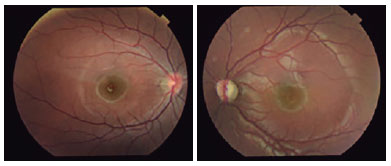

The patient is, V.G.C.S, an 11-year-old, previously healthy male who presents with a 2-year history of proptosis and progressive low visual acuity, worse in the left eye. There was no previous history of ophthalmologic disease. Ophthalmological examination showed better visual acuity of 20/25 in the right eye (RE) and light perception in the left eye (LE). Proptosis, limitation of adduction, hypertropia, and relative afferent pupillary defect were found in the LE. Biomicroscopy, tonometry, and gonioscopy findings were essentially normal in both eyes (BE). Fundoscopy of BE showed tilted optical discs with crescents of temporal atrophy and pallor in the LE disc (Figure 1). Optical coherence tomography (OCT) of the RE showed a sectoral nasal decrease in the macular layer of ganglion cells and in the layer of nerve fibers superior to the disc. OCT in the LE showed diffuse reduction in the thickness of both layers. There were no pathological systemic findings. Automated perimetry and MRI of the skull and orbits were requested. During perimetry, inferior temporal quadrantanopsia was observed in the RE and total scotoma was observed in the LE. MRI revealed an expansive and fusiform lesion (7.1 × 2.4 cm across the largest diameter) along the path of the optic nerve to the brainstem region with heterogeneous contrast uptake, suggestive of OPG, as well as asymmetrical lateral ventricles, larger on the right (Figure 2). The patient was referred to a neurosurgical service, with primary surgical management considered. Microsurgery with resection of an orbital and intracranial lesion was performed 1 month after diagnosis, without major complications. Histopathological diagnosis revealed grade 1 pilocytic astrocytoma based on the World Health Organization classification. Two months after surgery, the patient presented with a better visual acuity of 20/20 in the RE and light perception in the LE, orthotropy, without changes in ocular motility, with enophthalmos, and eyelid ptosis in the LE. Visual field testing revealed temporal hemianopsia in the RE and total scotoma in the LE.

03-fig01.jpg)